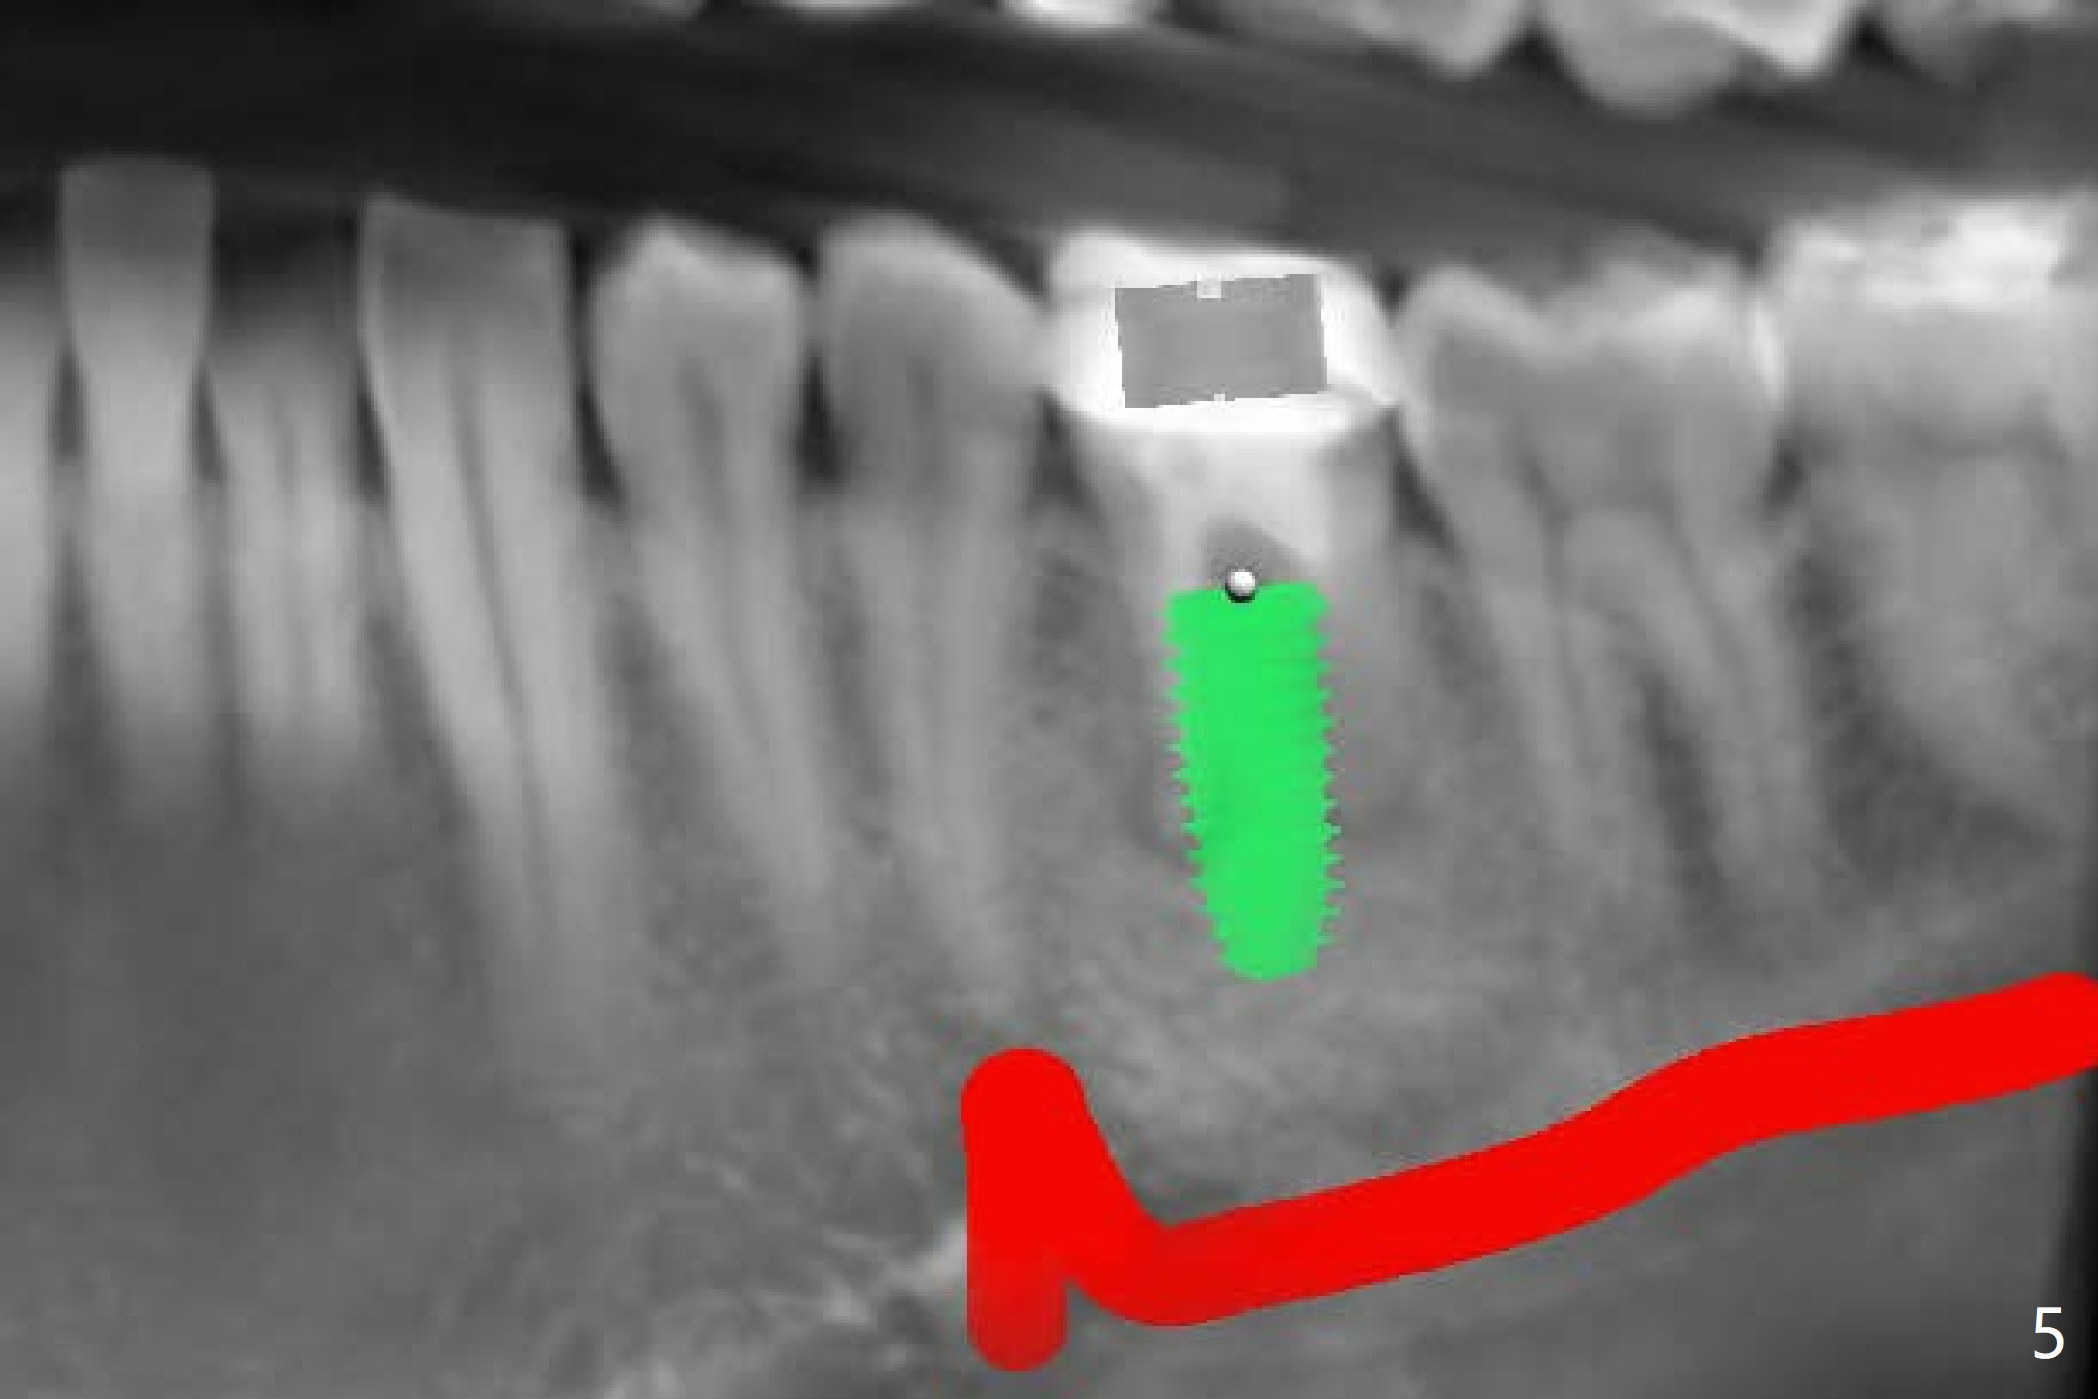

A 54-year-old man decides to extract the tooth #19 because of failure of RCT in the disto-lingual long curved root. Since it is difficult to drill through the roots, the latter will be removed. Use 2.2 mm drill to reach the depth first, look for deviation and take PA. Prepare cowhorn, surgical handpiece and proximators. PRFx1. Use 4.5x11.5 mm drill before placing 5.5x11mm IBS implant.